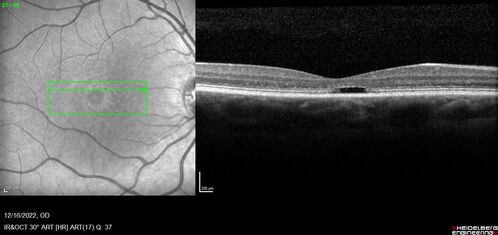

Stargardt Disease - Very Mild - 24 year old

This patient has 3 different ABCA4 mutations. His mother and sister have stargardts and his father has RP. His sisters images are also on Retinagallery.com